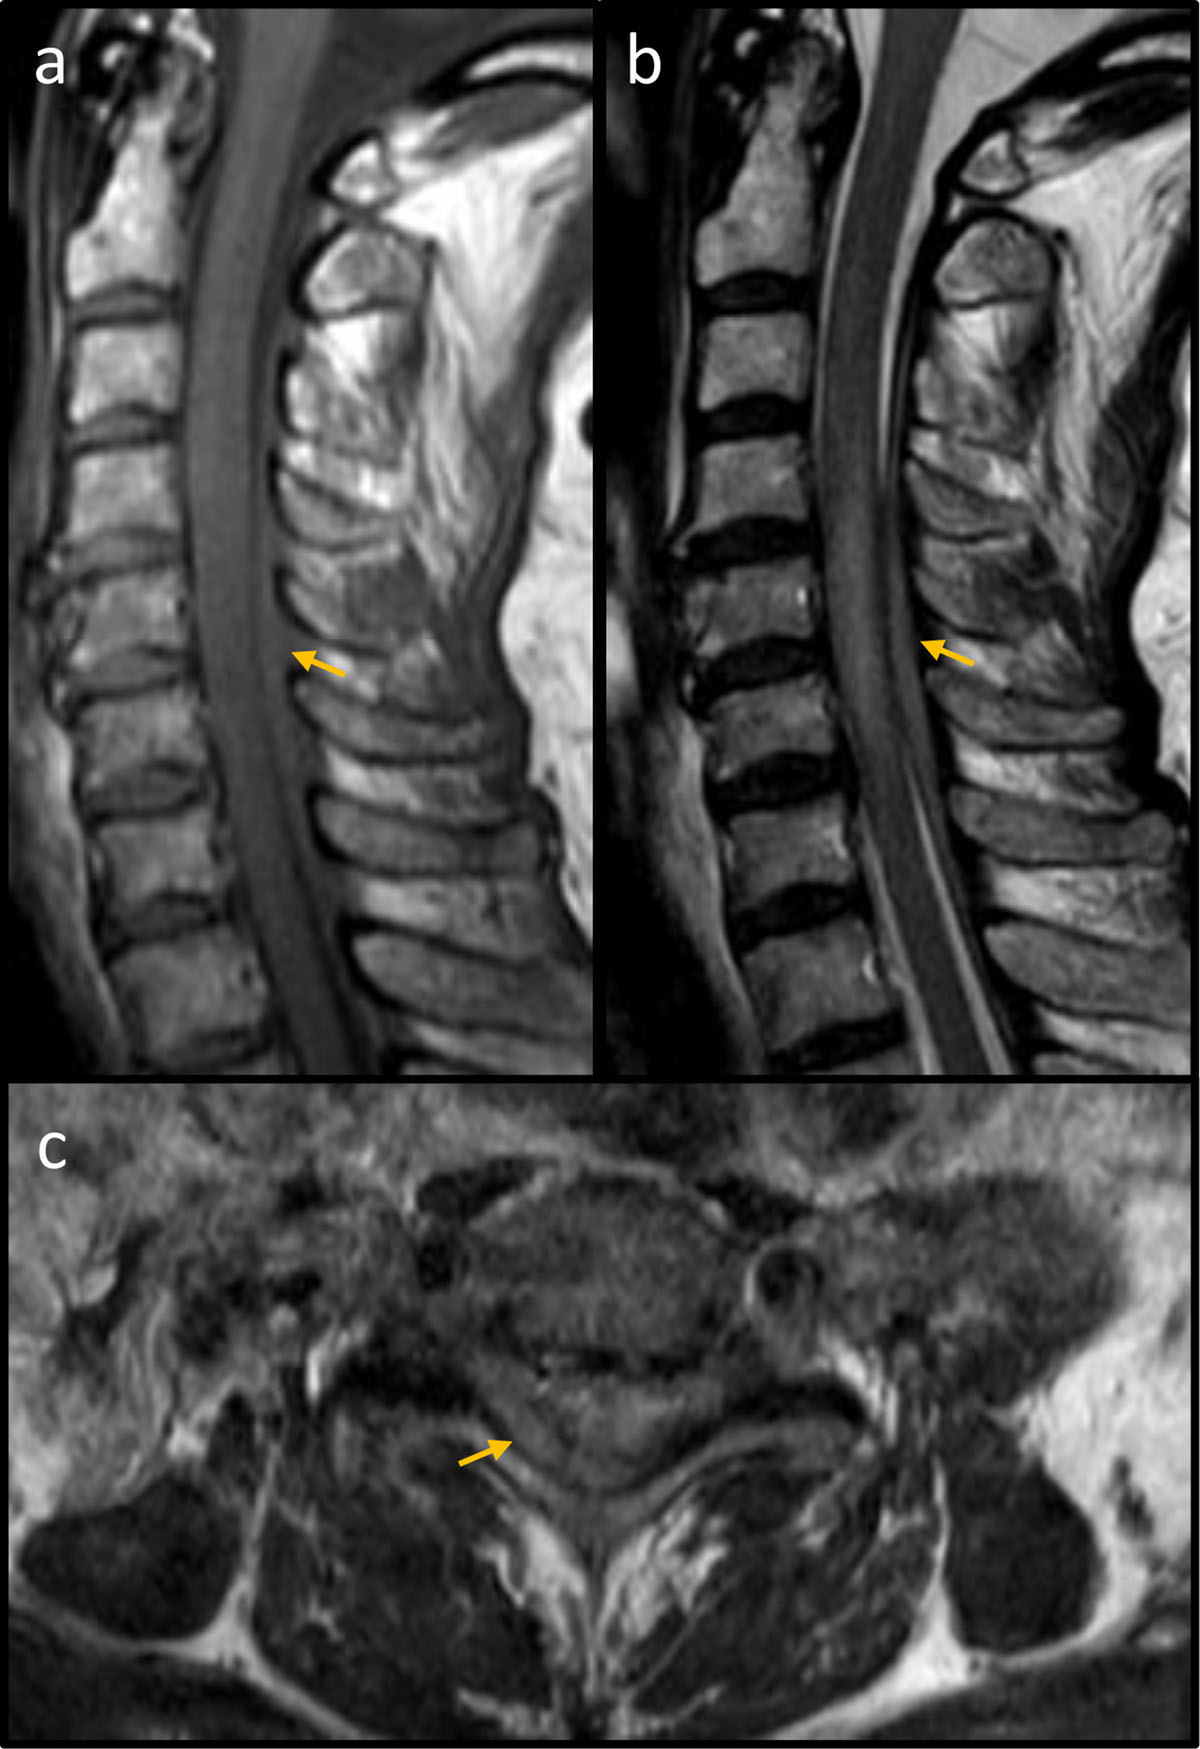

Figure 1

MRI of the cervical spine. (a) Sagittal T1 spin echo demonstrating an iso-intense space-occupying lesion (yellow arrow) restricted to the posterior epidural space. (b) Sagittal T2 spin echo showing a slightly hyper-intense mass (yellow arrow) in the posterior epidural space with corresponding myelopathy. (c) Axial T2 spin echo at vertebral level C6 showing a predominantly right-sided mass in the posterior epidural space (yellow arrow).

Unfortunately, the patient developed acute tetraplegia the first post-operative day. Magnetic resonance imaging (MRI) of the cervical spine revealed a space-occupying lesion in the posterior epidural space (Figure 1) with fusiform extension from C4 to C7. The spinal cord was found to be oedematous at the corresponding levels consistent with compressive myelopathy. An acute epidural hematoma was suspected, but during decompressive laminectomy a solid mass lesion was found and confirmed as lymphoma on histological examination.

Second, the radiological features of the lymphoma were erroneously interpreted as a hematoma. As for hematomas, the lymphoma in this patient strictly respected the anatomical boundaries of the epidural space, with normal (bony) posterior elements and no extension in either the intradural or interspinous spaces. In addition, the signal characteristics of an epidural lymphoma may resemble those observed in an hyperacute or acute hematoma on both T1- and T2 turbo spin echo-sequences, before the spontaneously bright T1-signal of methaemoglobin emerges in the subacute stage [4].